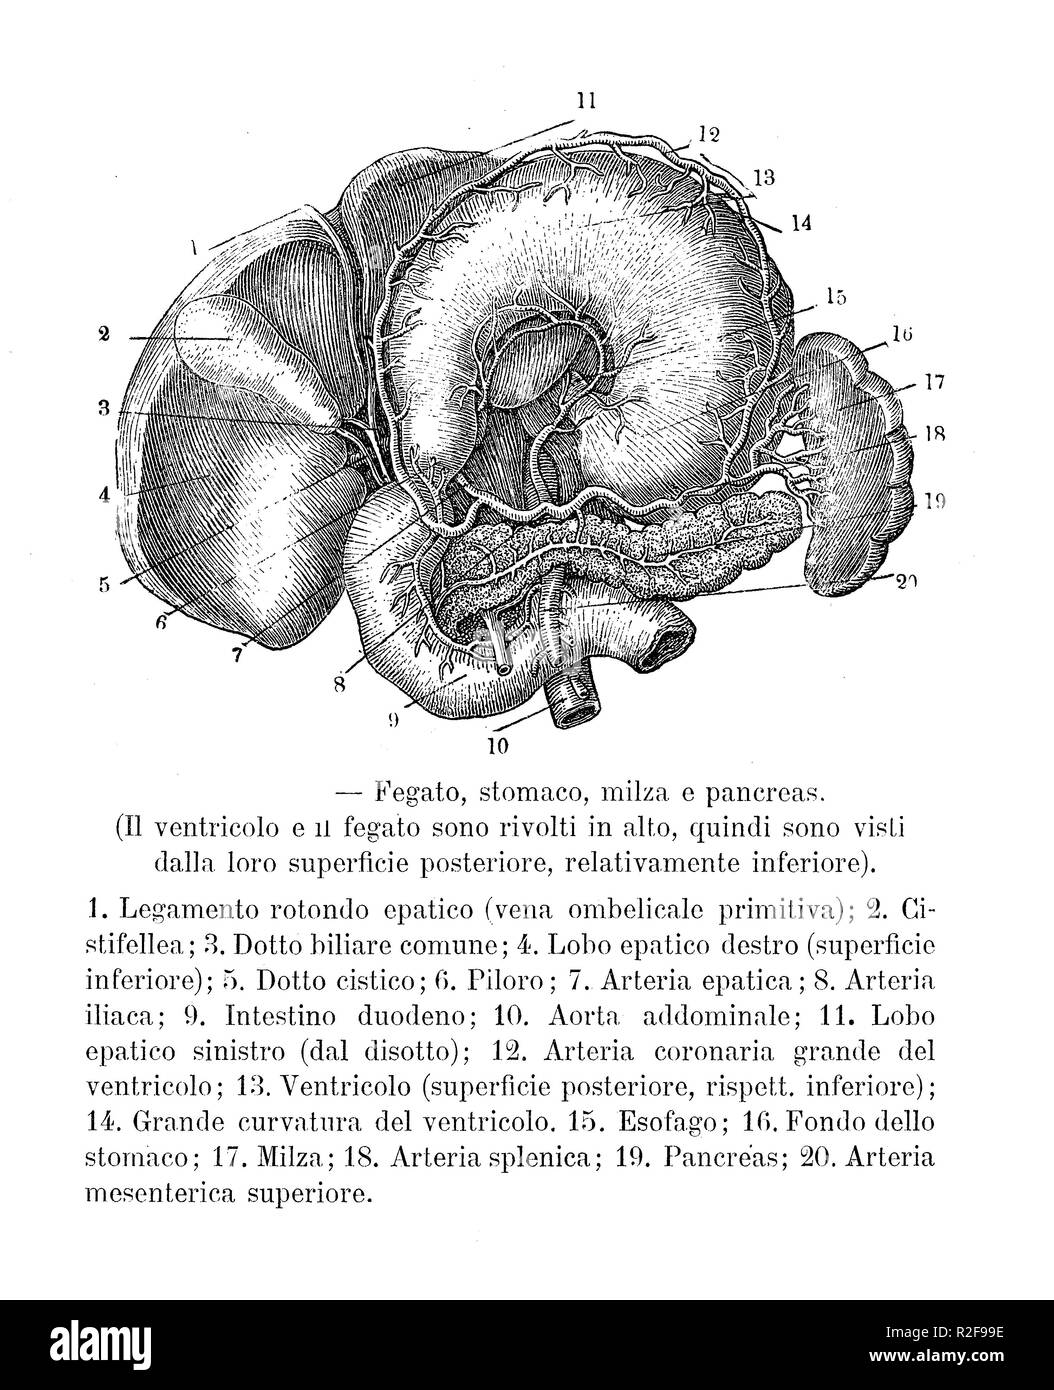

Vintage illustration of anatomy, human abdominal organs: liver,stomach, spleen and pancreas with Italian anatomical descriptions Stock Photohttps://www.alamy.com/image-license-details/?v=1https://www.alamy.com/vintage-illustration-of-anatomy-human-abdominal-organs-liverstomach-spleen-and-pancreas-with-italian-anatomical-descriptions-image225300698.html

Vintage illustration of anatomy, human abdominal organs: liver,stomach, spleen and pancreas with Italian anatomical descriptions Stock Photohttps://www.alamy.com/image-license-details/?v=1https://www.alamy.com/vintage-illustration-of-anatomy-human-abdominal-organs-liverstomach-spleen-and-pancreas-with-italian-anatomical-descriptions-image225300698.htmlRFR2F99E–Vintage illustration of anatomy, human abdominal organs: liver,stomach, spleen and pancreas with Italian anatomical descriptions